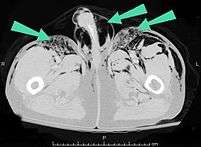

Signs and symptoms of spontaneous subcutaneous emphysema vary based on the cause, but it is often associated with swelling of the neck and chest pain, and may also involve sore throat, neck pain, difficulty swallowing, wheezing and difficulty breathing.[5] Chest X-rays may show air in the mediastinum, the middle of the chest cavity.[5] A significant case of subcutaneous emphysema is easy to detect by touching the overlying skin; it feels like tissue paper or Rice Krispies.[8] Touching the bubbles causes them to move and sometimes make a crackling noise.[9] The air bubbles, which are painless and feel like small nodules to the touch, may burst when the skin above them is palpated.[9] The tissues surrounding SCE are usually swollen. When large amounts of air leak into the tissues, the face can swell considerably.[8] In cases of subcutaneous emphysema around the neck, there may be a feeling of fullness in the neck, and the sound of the voice may change.[10] If SCE is particularly extreme around the neck and chest, the swelling can interfere with breathing. The air can travel to many parts of the body, including the abdomen and limbs, because there are no separations in the fatty tissue in the skin to prevent the air from moving.[11]

Subcutaneous emphysema is usually benign.[1] Most of the time, SCE itself does not need treatment (though the conditions from which it results may); however, if the amount of air is large, it can interfere with breathing and be uncomfortable.[29] It occasionally progresses to a state "Massive Subcutaneous Emphysema" which is quite uncomfortable and requires surgical drainage. When the amount of air pushed out of the airways or lung becomes massive, usually due to positive pressure ventilation, the eyelids swell so much that the patient cannot see. Also the pressure of the air may impede the blood flow to the areolae of the breast and skin of the scrotum or labia. This can lead to necrosis of the skin in these areas. The latter are urgent situations requiring rapid, adequate decompression.[30][31][32] Severe cases can compress the trachea and do require treatment.[33]

In severe cases of subcutaneous emphysema, catheters can be placed in the subcutaneous tissue to release the air.[1] Small cuts, or "blow holes", may be made in the skin to release the gas.[16] When subcutaneous emphysema occurs due to pneumothorax, a chest tube is frequently used to control the latter; this eliminates the source of the air entering the subcutaneous space.[2] If the volume of subcutaneous air is increasing, it may be that the chest tube is not removing air rapidly enough, so it may be replaced with a larger one.[8] Suction may also be applied to the tube to remove air faster.[8] The progression of the condition can be monitored by marking the boundaries with a special pencil for marking on skin.[33]